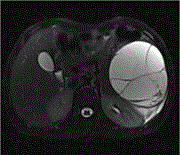

Giant retroperitoneal liposarcoma measuring 27 × 29 × 36 cm: a case report

Catalina Gutu and others

Journal of Surgical Case Reports, Volume 2023, Issue 1, January 2023, rjac608, https://doi.org/10.1093/jscr/rjac608